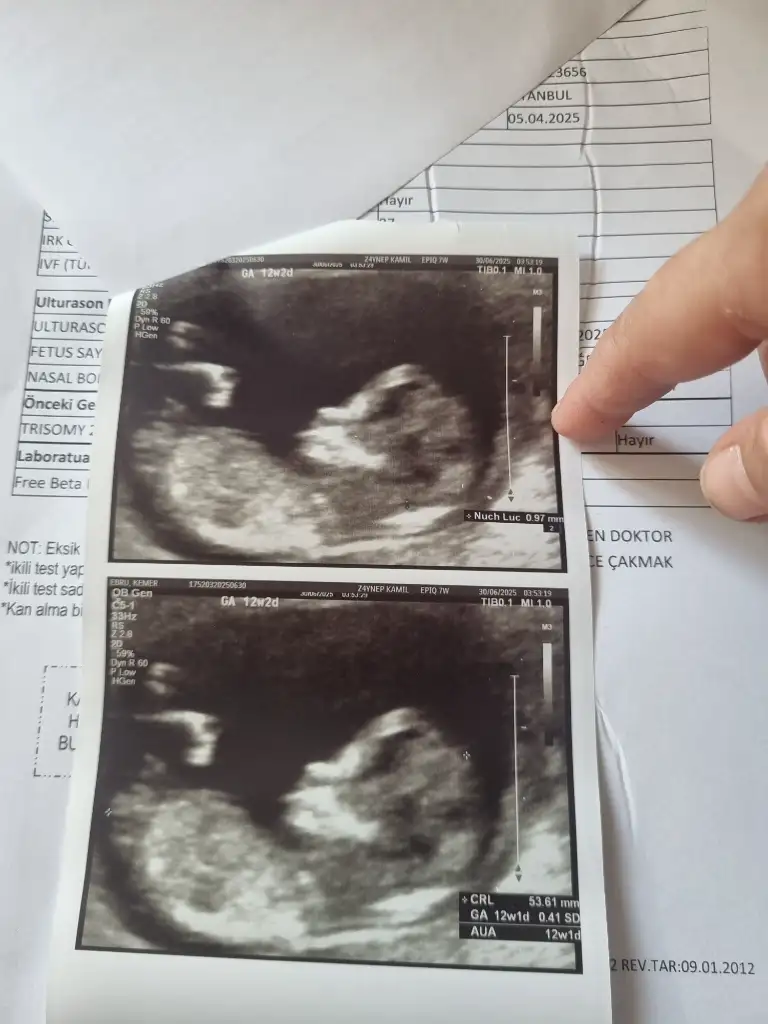

Bu ultrason da görünüyor mu nubUltroson fotoğrafından pek belli olmuyor sizin genelde nub teorisi doğru çıkıyor nub gözükmüyor sizinkinde

Bunda belli mi nubu sizce nedirUltroson fotoğrafından pek belli olmuyor sizin genelde nub teorisi doğru çıkıyor nub gözükmüyor sizinkinde

Erkek bence nubu çok görünmüyor ama tahminimBunda belli mi nubu sizce nedir

Kafa yapısı ve nub şeklinden anlıyorsunuz sanırımErkek bence nubu çok görünmüyor ama tahminim

Nub şekline göre yorum yaptım öğrenebildiniz miKafa yapısı ve nub şeklinden anlıyorsunuz sanırım

İlk resimde erkeğe benziyor ama kalça kemiği de olabilir dedi, 13 haftalık tam, bacağını kapatıyor, arkadan da boş görünüyor, pipi olsa arkadan görünür müNub şekline göre yorum yaptım öğrenebildiniz mi

Kız sanırım bacak arası boş görünüyor ben size benim resmi ekleyeyim videodan çektim 14 haftalıktı öğrendiğim deİlk resimde erkeğe benziyor ama kalça kemiği de olabilir dedi, 13 haftalık tam, bacağını kapatıyor, arkadan da boş görünüyor, pipi olsa arkadan görünür mü